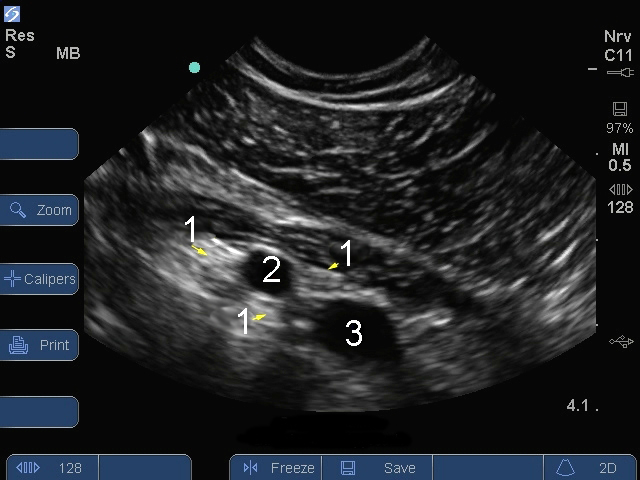

S Series:锁骨下臂丛图像

神经

动脉

静脉